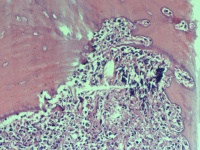

性别

男

年龄

74岁

腰骶部疼痛不适2月余 CT示骶髂处溶骨性改变伴周围软组织肿胀

骶髂处骨组织活检

1*1*0.5cm灰红碎组织

建议:CK;EMA;S-100等,排除脊髓瘤的可能性!(CT诊断什么?)

浆细胞性骨髓瘤或髓系肿瘤应考虑……